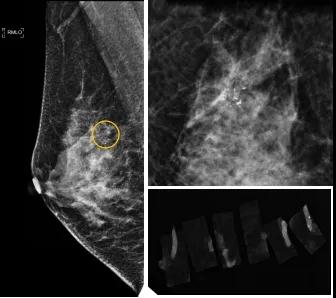

46歲的某女士在西安國(guó)際醫(yī)學(xué)中心醫(yī)院體檢時(shí),行乳腺X線攝影(俗稱鉬靶)發(fā)現(xiàn)右乳可疑簇狀鈣化,分布范圍不到1厘米,臨床觸不到,超聲很難發(fā)現(xiàn),但是這種鈣化風(fēng)險(xiǎn)比較高,依據(jù)國(guó)際BI-RADS指南需要明確病理!

西安國(guó)際醫(yī)學(xué)中心醫(yī)院影像診療中心陳寶瑩副主任帶領(lǐng)的團(tuán)隊(duì),采用全數(shù)字化乳腺X線三維立體定位系統(tǒng)可實(shí)施。這個(gè)團(tuán)隊(duì)的成員大部分來自知名三甲醫(yī)院,有著十余年影像引導(dǎo)下乳腺介入診療的經(jīng)驗(yàn),X線引導(dǎo)穿刺定位和活檢例數(shù)居西北前列。為減少患者創(chuàng)傷,在詳細(xì)判讀了患者資料,并與患者及甲乳外科劉曉敏主任充分溝通的基礎(chǔ)上,團(tuán)隊(duì)確定采用全數(shù)字化乳腺X線三維立體定位系統(tǒng)下實(shí)施粗針活檢。

當(dāng)天,乳腺X線三維立體定位系統(tǒng)清晰顯示出了所有鈣化。為了獲取充足的組織量,保證病理診斷的準(zhǔn)確性,團(tuán)隊(duì)選用14G穿刺針并多點(diǎn)、多角度取材,組織取出后,又立即在高清標(biāo)本攝影系統(tǒng)中進(jìn)行投照,從而確定了取出組織中具有足夠的可疑鈣化。整個(gè)過程患者無任何不適,活檢結(jié)束后即回家觀察。